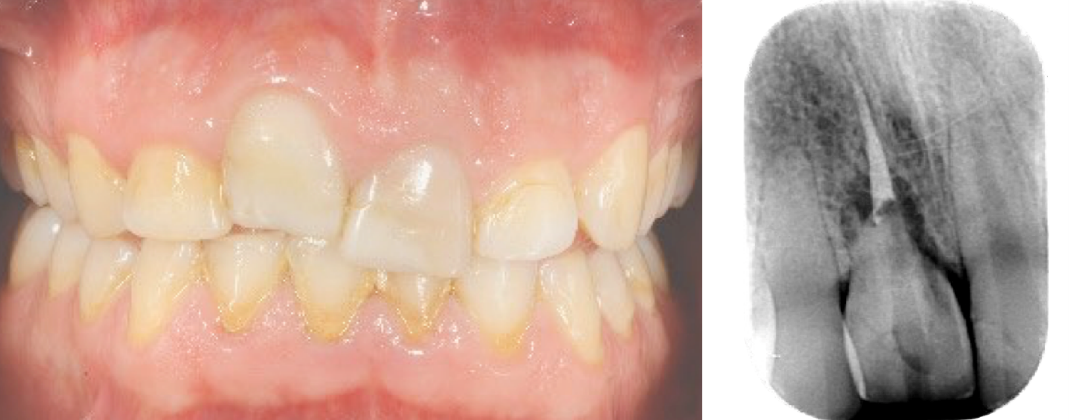

Immagine clinica iniziale ed evidenza radiografica del riassorbimento radicolare